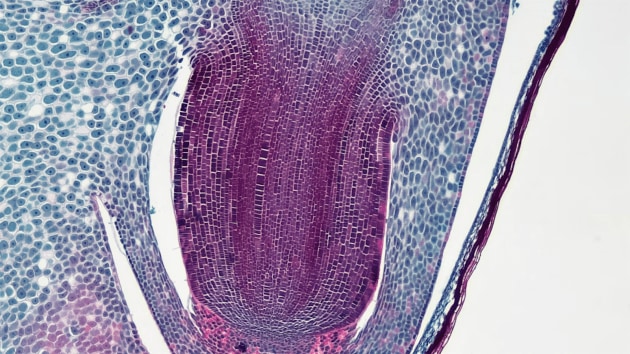

Familial Adenomatous Polyposis (FAP): This inherited condition causes hundreds of polyps to form in the colon and rectum, often leading to cancer if not treated early. (Source: Photo by unsplash)